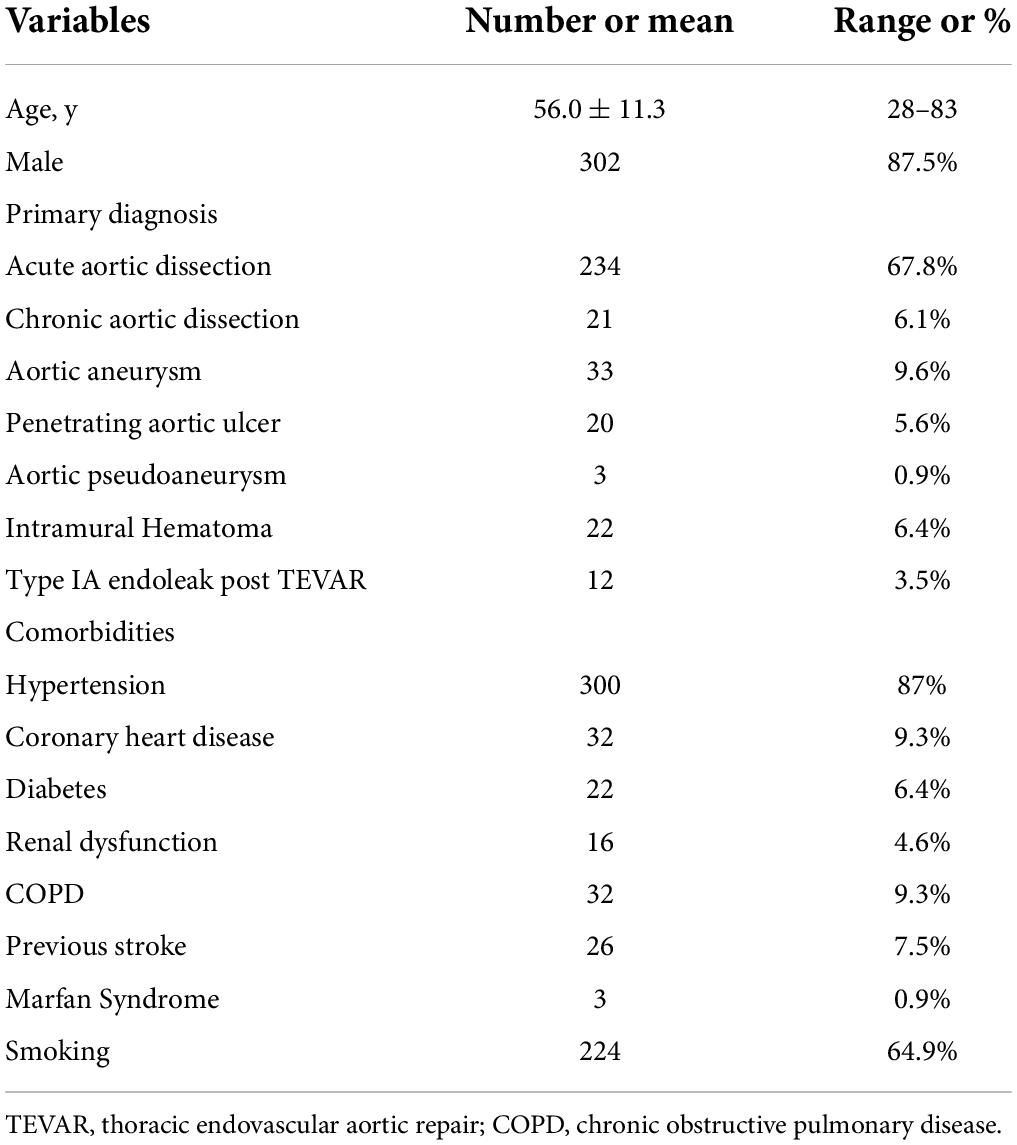

As shown in Figure 1, there were different types of cTEVAR performed in our study. 278 (80.6%) patients received single chimneys, including 50 in LCCA and 228 in LSA. A total of 53 patients (15.4%) underwent the double-chimney procedure, among whom 20 had chimney stents deployed in an IA and LCCA, 31 in LCCA and LSA, and 2 in LSA and aberrant right subclavian artery (aRSA). There were seven (2%) patients who received triple chimneys in the IA, LSA, and LCCA. Besides these conventional chimney procedures, seven (2%) patients received cTEVAR accompanied with other techniques, among whom two received LCCA chimney and LSA-RSA bypass, while five received cTEVAR accompanied with fenestration (two with in situ fenestration and three with physician modified fenestration). Therefore, a total of 412 chimney stents were used, including 27 in IA, 113 in LCCA, 270 in LSA, and 2 in aRSA. The flow in 383 (93.%) chimney stents was in the same direction as the aortic flow, while the flow of 29 (7%) chimney stents was in the reverse direction of the aortic flow, which was also known as the “periscope” technique. The aortic stent-grafts were landed proximally in zone 0 (n = 27), zone 1 (n = 86) or zone 2 (n = 232). A total of 28 (8.1%) patients received more than one aortic stent-graft. Finally, six (1.7%) patients received endovascular repair of thoracic and abdominal aortic lesions simultaneously. The operative details were summarized in Table 2.

Figure 1. Different types of cTEVAR in the study. (A,B) Chimney stent in LSA; (C,D) snorkel stent in LSA; (E,F) chimney stent in LCCA; (G,H) chimney stent in LSA and snorkel stent in aRSA; (I,J) chimney stents in LCCA and LSA; (K,L) chimney stent in LCCA and snorkel stent in LSA; (M,N) chimney stents in IA and LCCA; (O,P) chimney stents in IA and LCCA, and snorkel stent in LSA. cTEVAR, TEVAR with chimney; IA, innominate artery; LCCA, left common carotid artery; LSA, left subclavian artery; aRSA, aberrant right subclavian artery.